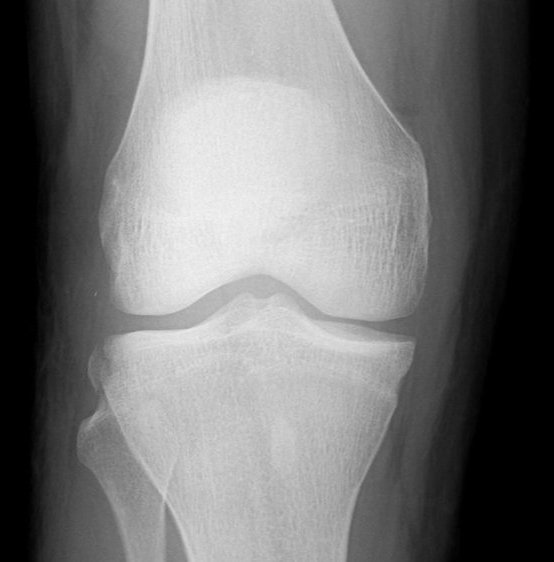

Segond Fracture

This is a very subtle "avulsion fracture of the tibia below the articular margin" caused by traction on the capsular or coronary ligaments. It is not possible to cause this fracture without first rupturing at least one of the major ligaments in the knee.

The classical description1 is limited to the lateral side where associated injuries include:-

The reverse Segond fracture describes similar lesions on the medial side associated with ER+Valgus injuries: -

Examples in order of increasing subtlety: -